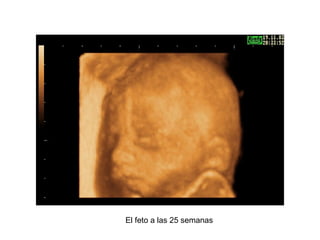

Las ecografías 3D han avanzado mucho la ciencia, permitiendo ahora distinguir claramente al feto a diferentes etapas de desarrollo como las 9, 13, 25 y 30 semanas de gestación, mostrando su progresivo crecimiento hasta convertirse en un adulto a los 18 años.